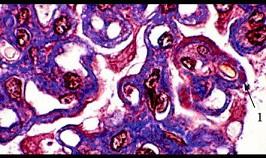

问题 图-1显微镜下嗜银染色,可见膜性肾小球肾炎时黑色的基底膜物质突出于毛细血管袢周围,呈特征性的“火焰”状(钉突形成), 图-2GBM弥漫性增厚,上皮下多数嗜复红蛋白沉积(1)(Masson), 图-3上皮下多数电子致密物沉积(D),上皮细胞足突广泛融合,GBM增厚(电镜),符合该诊断的病理为 ( )

选项 A、Ⅳ期膜性肾病 B、Ⅴ期膜性肾病 C、Ⅰ期膜性肾病 D、Ⅲ期膜性肾病 E、Ⅱ期膜性肾小球肾炎

答案 E